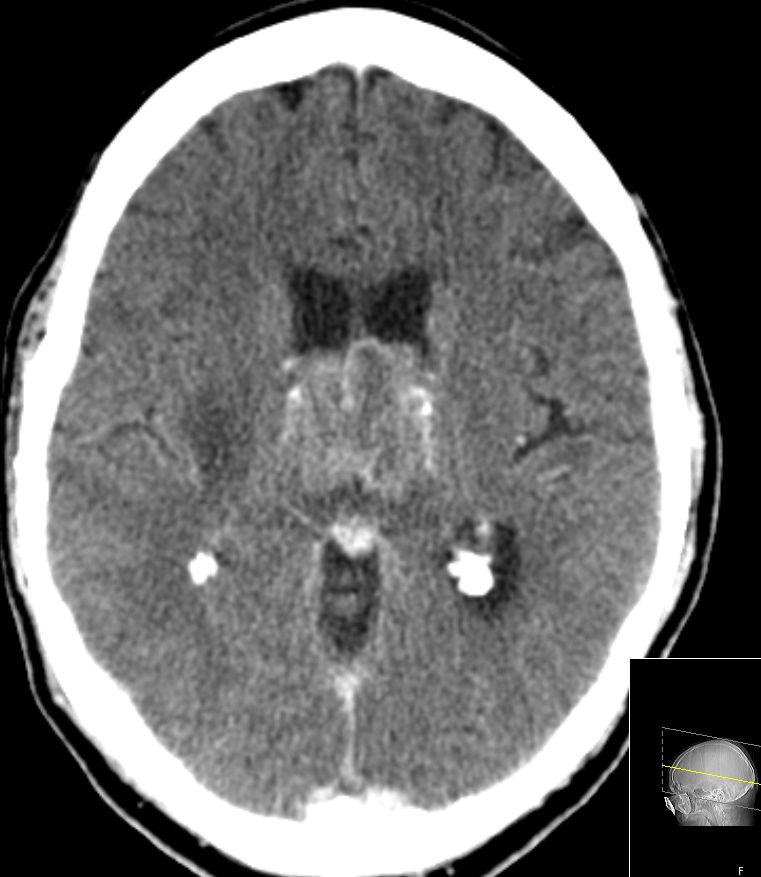

| CT: multiple Hirnmetastasen | Adenokarzinom der Lunge. CT-Untersuchung des Hirns mit Kontrastmittel. | |||

![]() |

![]() | |||